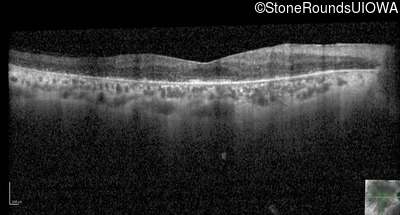

Optical Coherence Tomography - Right - 20/30

Exemplar / OCT Stack

OCT Stack